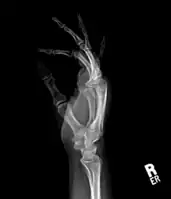

Medical imaging usually shows a well-defined wide-based bony growth on the surface of bone.[5] It can be pedunculated and irregular, giving it a "bizarre" appearance, and is not connected to underlying bone.[2]

X-ray left foot: Bizarre parosteal osteochondromatous proliferation in 2nd toe

X-ray hand, BPOP 2nd metacarpal

X-ray hand, BPOP 2nd metacarpal (side view)